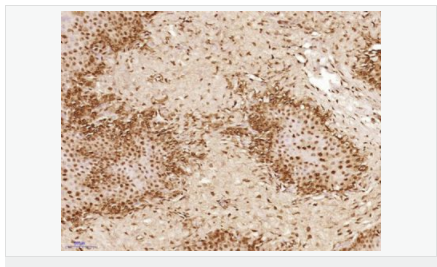

產(chǎn)品應(yīng)用IHC-P=1:100-500 IHC-F=1:100-500 ICC=1:100-500 IF=1:100-500 (石蠟切片需做抗原修復(fù))

細(xì)胞定位細(xì)胞核 細(xì)胞漿